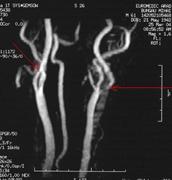

ARM arata la nivelul vaselor precerebrale:

stenoza strānsa la nivelul ACI stāngi

stenoza larga la nivelul ACI drepte

absenta AV stāngi.

Intracranian, ARM evidentiaza:

leziuni ATS multiple

absenta A1 dr

hipoplazia P1 bilateral